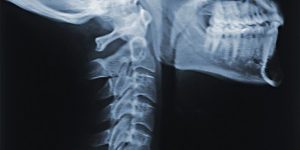

Reliable Tech News urgently warns all our readers: there are health problems related to the use of tech equipment. Whether texting on your cell phone or bending over your computer, you will create big problems for yourself just by the degree you tilt your head. Tech neck!

Kept at the normal 90° your head weighs a remarkable 12 lb! But if you tilt to text, head weight greatly increases and so does the effect of tech neck. Of course, not the actual weight, but the weight of strain placed on neck and back muscles. It’s-as-though there was 42 lbs of weight pulling on these muscles due to improper support. Improper support that produces the pain of tech neck.